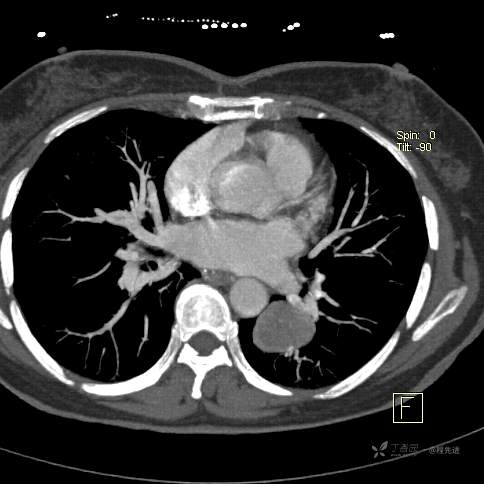

患者性别:女

患者年龄:57岁

简要病史:体检发现

CT增强

平扫CT值约40HU(未上传图像),增强后动脉期CT值约70HU,静脉期CT值约97HU。

肺硬化性血管瘤 (20)